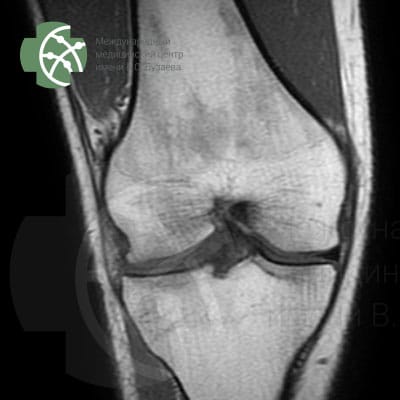

MRI of the knee joint

Magnetic resonance imaging of the knee joint without contrast agent

Our MRI knee joint protocol includes the following sequences:

Program / slice thickness

PD FS saggital 3 mm

T2 saggiati 3 mm

T2 FS saggital 3 mm

PD FS coronal 3 mm

T1 coronal 3 mm

PD FS axial 3 mm

MERGE saggital 3 mm